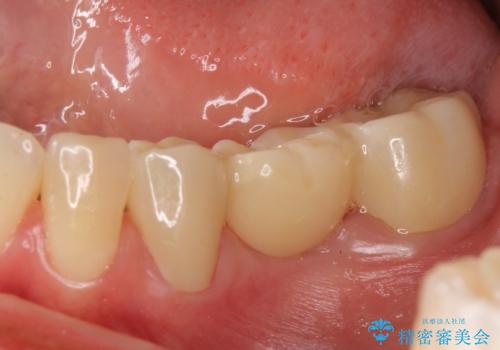

途中全体矯正をはさみ、根の向きが並行になった状態でブリッジを入れることができました。

- 36.3万円 (ジルコニアクラウン 10万円×3、仮歯1万円×3)費用は治療当時の料金となります